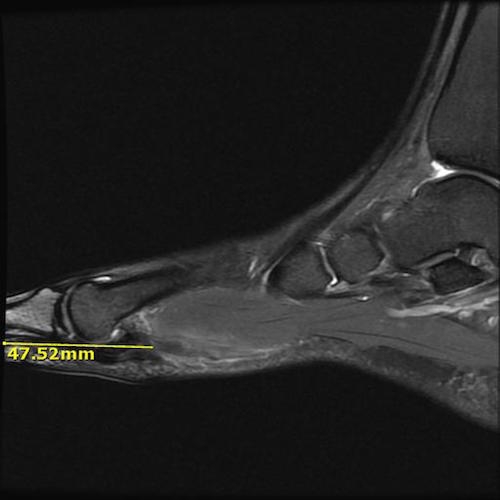

MRI

Chronic FHL tendon rupture in the arch area. No evidence of flexor hallicus brevis disruption. The sesamoids are intact. Sagittal with measurement Case Photo #5 , Sagittal Case Photo #6 , Axial with measurement Case Photo #7 , Axial Case Photo #8